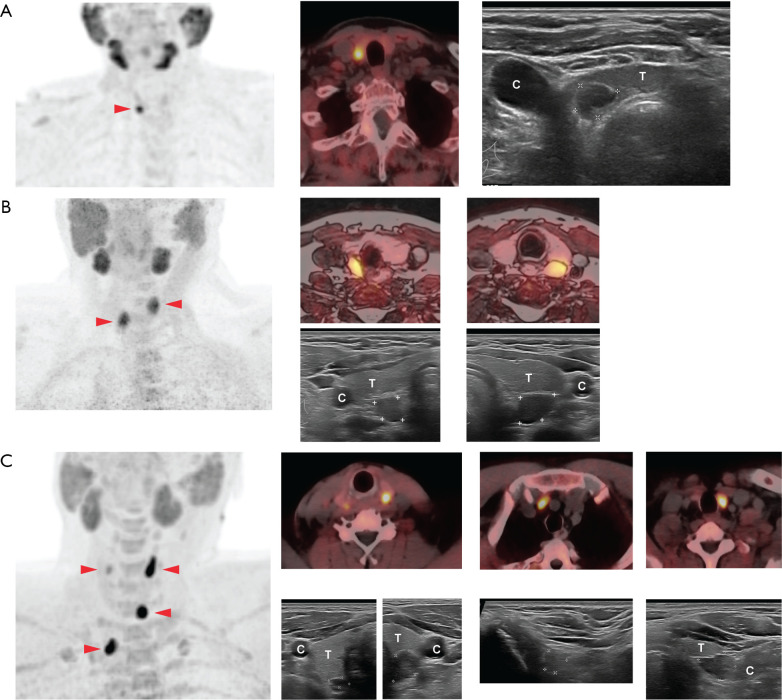

Background: Positron emission tomography (PET) with fluorine-18 or carbon-11 labeled choline (choline PET) has been found to have higher diagnostic accuracy for localizing hyperfunctioning parathyroid glands than other imaging methods. To evaluate if ultrasound (US) still has value in the diagnostic workup, we compared the findings on choline PET with US findings in patients with hyperparathyroidism (HPT).

Methods: We retrospectively reviewed all patients with HPT who underwent a choline PET in the University Hospital of North Norway between 2019-2022. The indications for choline PET were negative or inconclusive localization with [99mTc]Tc-sestamibi scintigraphy and US, previous parathyroid surgery, or suspicion of multiglandular disease. Additionally, a focused parathyroid US was performed either before (67% of patients) or after the choline PET, without any blinding between modalities.

Results: Sixty-two patients were included, of which 50 had been operated on at the time of analysis. Parathyroid tissue was removed in all patients, and multiglandular disease was found intraoperatively in 15 patients (30%). 96% of patients became normocalcemic after surgery. Diagnostic accuracy for choline PET and US was 98% and 89%, respectively, and 100% combined. Multiglandular disease was detected in 28% of patients by both modalities. Two patients with negative choline PET had a true positive US finding.

Conclusions: Choline PET in combination with US performed by a radiologist specialized in neck US, successfully localized parathyroid disease in all operated patients. Both modalities detected 28% multiglandular disease. Findings on choline PET had better correspondence with intraoperative findings than US.